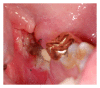

Infections are increasingly considered as potential trigger for carcinogenesis apart from risk factors like alcohol and tobacco. The discussion about human papilloma virus (HPV) in oral squamous cell carcinoma (OSCC) points at a general role of infection for the development of oral carcinomas. Furthermore, first studies describe a correlation between chronic periodontitis and OSCC, thus, characterizing chronic inflammation as being a possible trigger for OSCC. In front of this background, we present four well-documented clinical cases. All patients showed a significant anatomical relation between OSCC and clinical signs of chronic periodontitis. The interindividual differences of the clinical findings lead to different theoretical concepts: two with coincidental appearance of OSCC and chronic periodontitis and two with possible de novo development of OSCC triggered by chronic inflammation. We conclude that the activation of different inflammatory cascades by chronic periodontitis negatively affects mucosa and bone. Furthermore, the inflammatory response has the potential to activate carcinogenesis. Apart from a mere coincidental occurrence, two out of four patients give first clinical hints for a model wherein chronic periodontitis represents a potential risk factor for the development of OSCC.